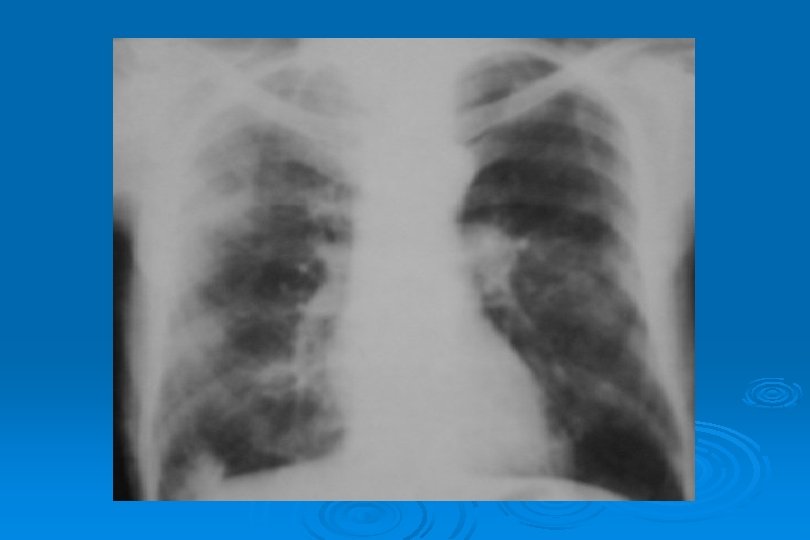

BRONKOPNÖMONİ Mikroorganizma veya infekte materyalin bronş ve bronşiol epiteline yerleşmesi ve ülserasyona neden olması Ø Grafide yamalı konsolidasyon saptanır zamanla lober pnömoni olabilir Ø En sık S. aureus, M. tuberculosis, Gr(-) bakteriler, anaerobik bakteriler, L. Pneumophila’dır Ø S. pneumoniae, H. influenza ve P. aeruginosa Ø

İNTERSTİSYEL PNÖMONİ Ø Bakteriyel interstisyel pnömoni oldukça seyrektir Ø M. pneumoniae en sık rastlanılan etkendir Ø H. influenza, Branhamella catarrhalis, C. pneumoniae, C. trochomatis ve S. pneumoniae

İNTERSTİSYEL PNÖMONİ Ø İnce retiküler patern Ø Daha sonra milier veya retikülonodüler patern ve peribronşial kalınlaşmaya bağlı olarak bronkovasküler görünümlerde belirginleşme

İNTERSTİSYEL PNÖMONİ Ø Hastalık ilerledikçe bronkovasküler görünüm ( yamalı infiltrasyon) ortaya çıkar Ø En sık alt lobları, sol akciğeri tutar Ø Genelde tek lob tutulur